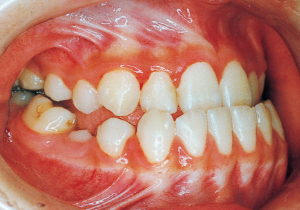

2 After Phase 2 Treatment 5-9-’92

Aware that treatment would be challenging, we proceeded with the first phase of treatment based on the current functional status and anticipated developmental implications (7). During the mixed dentition phase, the body responds readily to treatment, allowing for relatively rapid tooth movement and changes in jaw position (8,9). Subsequently, once freed from mechanical stimulation, growth continues according to inherent predispositions, often appearing to disregard occlusal functional efficiency (10,11). These changes are clearly observable on cephalometric radiographs (12). After confirming the extent and direction of growth, we decided to incorporate surgical intervention into the treatment plan and wait until the age when growth begin to decline.

16 5-9-’92 After Phase 2 Treatment

17 8-15-’94 After Retention 14 years and 7 months after start of treatment